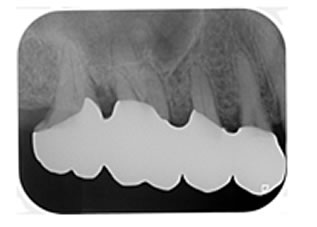

症例3

治療の特徴(患者I様)

初診 2015年5月1日 / 経過 2018年7月2日

| 治療期間 | 2年5カ月(2019年5月時点SPT中) |

|---|---|

| 費用 | 保険内治療 |

| 歯間外科処置 | 1ブロック約9,000円(3割負担) |

| 治療のデメリット | 外科処置を伴う・治療期間が長い(歯槽骨の安定を見る為) 歯周 外科処置後歯肉の位置が下がる為知覚過敏が起こりやすい |

症例4

初診時においては物を咬むと違和感が強く歯周外科処置を行いました。

骨のラインが部分的に増え、平坦にきれいに治っています。

2019年5月20日現在